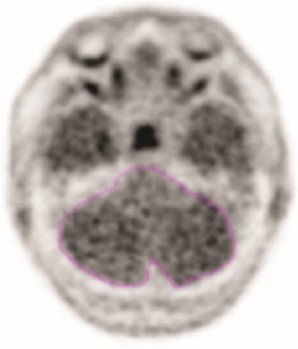

Registrera genomsnittlig aktivitet eller cerebellära värden (MCC). Området av intresse ska markeras med skanningen i gråskala och i axialplanet som exemplet i figur 1 visar.

Figur 1: Exempel på område av intresse i cerebellum